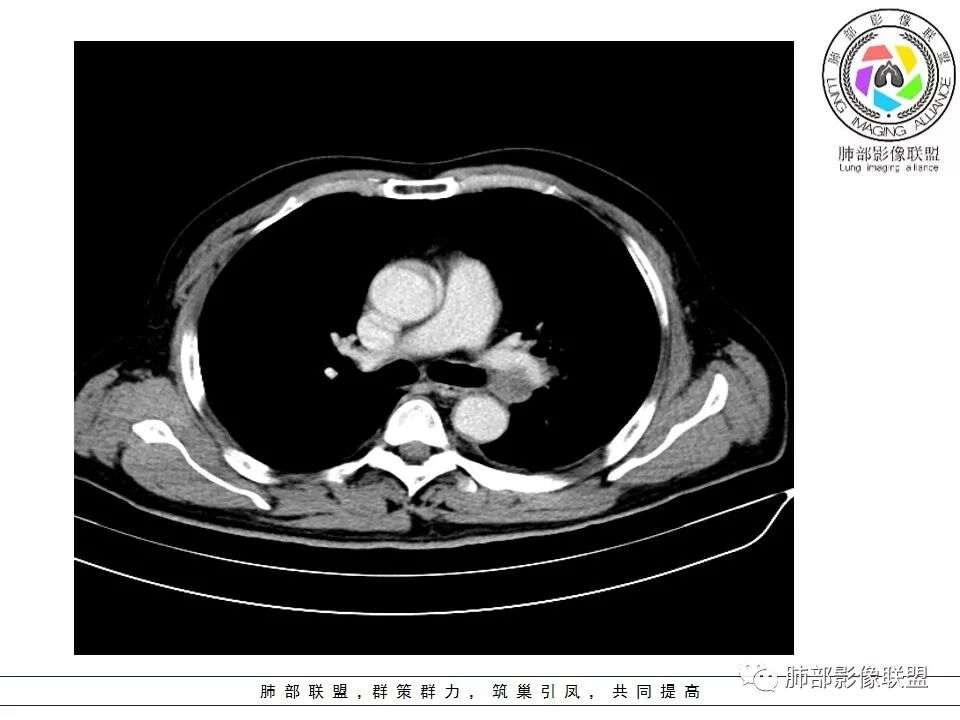

2娘小崽大、淋巴及血行转移早、冰冻纵隔及肺门血管脂肪间隙消失

因为病灶侵袭力强,病灶易沿淋巴道、间质及心血管间隙等结构侵犯并密切挤压上述结构,常常能够观察到脂肪间隙消失。易于出现冰冻纵隔。原发灶与肺门转移灶可形成哑铃状外观,甚至转移灶体积大于周围原发灶,有人称之为“娘小崽大”。早期病灶有时很小甚或隐匿,仅能看到转移灶,或转移淋巴结与原发灶融合分界不清。病变向肺门延续的串珠样淋巴结转移也是SCLC的典型特点。

血管包埋征

病灶侵袭力强大,早期沿粘膜下疏松结缔组织及血管旁间隙扩散,包绕血管,血管会受压变形,因为小细胞癌破坏力弱,血管没有被破坏,所以仅仅表现为包埋浸润,但血流面光滑。

1.左肺下叶近肺门区肿块,肿块外围大,内带小,提示外围向中央生长,符合周围型SCLC沿支气管方向生长。

5.病灶内有血管走行,血管局部受压,但是强化考虑为乏血供,提示病灶内肺动脉并不是供血血管,只是病灶侵袭性强把血管包埋而已,为血管包埋征;血流面光滑,血管包埋符合SCLC。

6.左肺门淋巴结肿大,与病灶局部融合分界不清,呈冰冻肺门;而纵隔内未见肿大淋巴结,冰冻肺门符合SCLC,但是病灶主体那么大,纵隔内没有明显肿大淋巴结,不是很符合SCLC娘小崽大的特点。